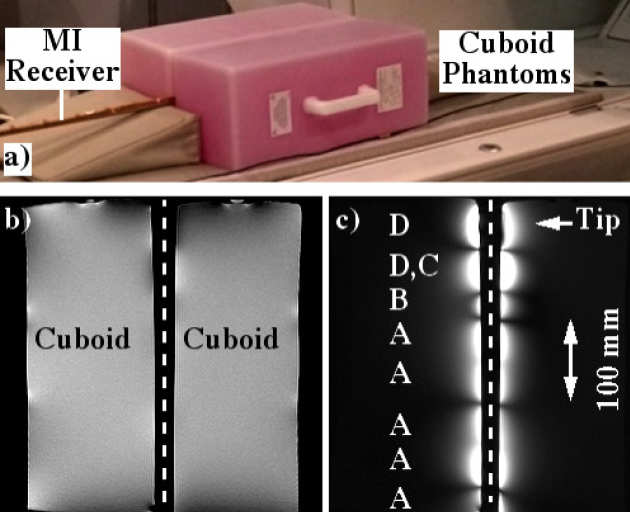

Richard Syms, Evi Kardoulaki and Ian Young

Simon Taylor-Robinson, Chris Wadsworth and Marc Rea (St Mary’s Hospital)

We have developed a magnetic resonance imaging duodenoscope, by combining non-magnetic endoscope components with a thin-film receiver based on a magneto-inductive waveguide. The waveguide elements consist of figure-of-eight shaped inductors formed on either side of a flexible substrate and parallel plate capacitors that use the substrate as a dielectric. Operation has been simulated using equivalent circuit models and by computation of sensitivity patterns. Circuits have been fabricated for operation at 127.7 MHz by double-sided patterning of copper-clad Kapton and assembled onto non-magnetic flexible endoscope insertion tubes. Operation has been verified by bench testing and by 1H MRI at 3T using phantoms. The receiver can form a segmented coaxial image along the length of the endoscope, even when bent, and shows a signal-to-noise-ratio advantage over a surface array coil up to three times the tube diameter at the tip. Initial immersion imaging experiments have been carried out and confirm an encouraging lack of sensitivity to RF heating.

|

|---|

| Arrangement for magnetic resonance imaging with cuboid phantoms (a), body coil image showing effective decoupling (b) and metamaterial coil image, showing segmented field of view (c). |